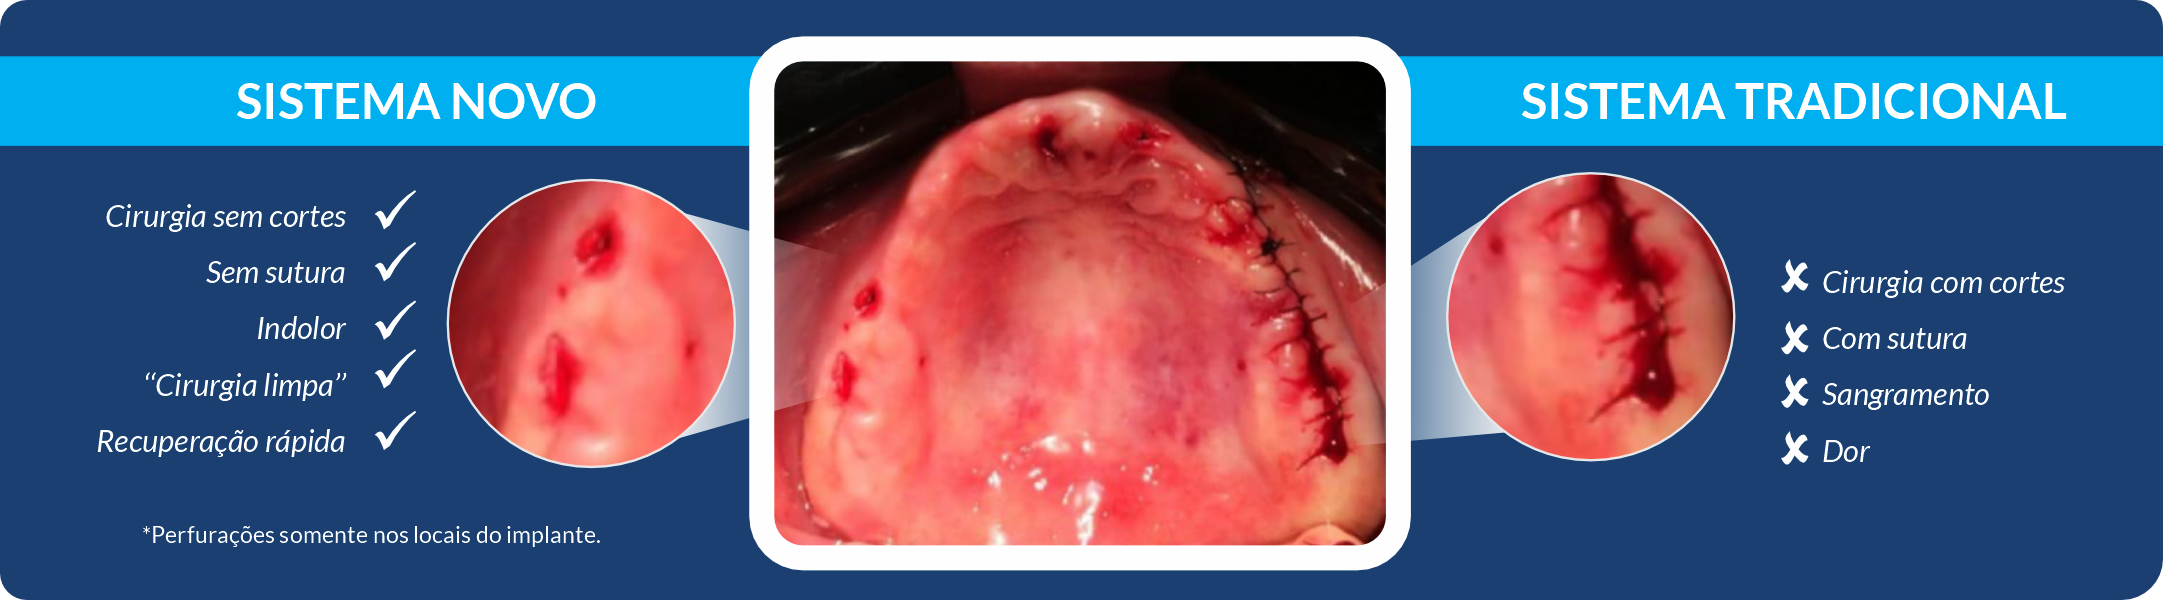

É o procedimento da realização de implante(s) de maneira guiada, com total segurança, uma cirurgia com possibilidade de não haver cortes, reduzido sangramento e pós-operatório rápido e na grande maioria das vezes totalmente indolor. Para obter o guia é necessário fazer tomografia e escaneamento da arcada dentária. Com esses exames e um software de planejamento será feito o planejamento em 3D dos implantes e gerado uma guia de implantes, a qual será posicionado em boca para direcionar a correta perfuração e instalação dos implantes. A precisão do posicionamento dos implantes com o uso do guia, permite, além dos benefícios cirúrgicos, que o(s) dente(s) da prótese já possam ser confeccionados previamente, e já estarem prontos para serem instalados no dia da cirurgia.